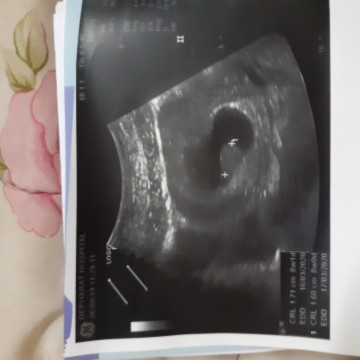

9w ค่ะ